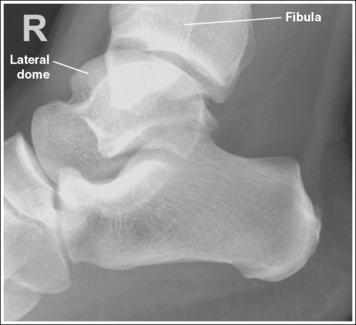

The ankle is in a lateral projection. The domes of the talus are superimposed, the tibiotalar joint is open, and the distal fibula is superimposed by the posterior half of the distal tibia.

• To obtain a lateral ankle projection, begin with the patient in a supine position, with the leg extended (Figure 6-57) and the foot dorsiflexed until its long axis forms a 90-degree angle with the lower leg. Rotate the patient and affected leg until the lateral foot surface is against the IR, and then adjust the degree of rotation until the surface is aligned parallel with the IR (Figure 6-58). For most patients, this positioning places the lower leg parallel with the imaging table. If this is not the case, as with a patient with a large upper thigh, the foot and IR should be elevated until the lower leg is parallel with the imaging table.

• Effect of lower leg positioning on talar dome superimposition. Often, if the knee is not fully extended (Figure 6-59) or if the distal tibia is not elevated to place the lower leg parallel with the IR in a patient with large upper thighs, the proximal tibia is positioned farther from the imaging table than the distal tibia. The resulting image demonstrates the lateral talar dome proximal to the medial talar dome and the height of the longitudinal arch appears less than it actually is because the cuboid shifts anteriorly and the navicular bone moves posteriorly in this position and the talocalcaneal joint will be narrowed (see Image 43). If the distal tibia is positioned farther from the table than the proximal tibia, the medial talar dome is demonstrated proximal to the lateral dome, and the height of the longitudinal arch appears greater than it actually is because the cuboid shifts posteriorly and the navicular bone moves anteriorly in this position and the talocalcaneal joint will be widened (see Image 44). When viewing a lateral ankle projection that demonstrates one of the talar domes proximal to the other, evaluate the height of the longitudinal arch and the degree of talocalcaneal joint visualization to determine which dome is the proximal dome. If the navicular bone is superimposed over more of the cuboid than expected and a narrowed talocalcaneal joint is seen, the lateral dome is the proximal dome. If the navicular bone is superimposed over less of the cuboid than expected and a wider talocalcaneal joint is seen, the medial dome is the proximal dome.

• Effect of foot positioning on talar dome superimposition. To demonstrate accurate AP alignment of the talar domes, position the lateral surface of the foot parallel with the IR. If this surface is not parallel with the IR, the talar domes are demonstrated one anterior to the other. When the leg is rotated more than needed to place the lateral foot surface parallel with the IR (leg externally rotated), as shown in Figure 6-60, the medial talar dome is demonstrated anterior to the lateral talar dome (see Image 45). If the leg is not rotated enough to place the lateral foot surface parallel with the IR (leg internally rotated), as shown in Figure 6-61, the medial talar dome is demonstrated posterior to the lateral talar dome (see Image 46). When taking a lateral ankle projection that demonstrates one of the talar domes anterior to the other, observe the position of the fibula in relation to the tibia to determine how the patient should be repositioned. On most lateral ankle projections with accurate positioning, the fibula is positioned in the posterior half of the tibia. On a lateral projection with poor positioning, if the fibula is demonstrated more posteriorly, the medial dome is anterior and the patient was positioned with the forefoot depressed and the heel elevated (leg externally rotated), as shown in Figure 6-60. If the fibula is demonstrated more anteriorly, the medial domes are posterior and the patient was positioned with the forefoot elevated and the heel depressed (leg internally rotated), as shown in Figure 6-61.

The long axis of the foot is positioned at a 90-degree angle with the lower leg.

• In most cases, when the patient is relaxed, the foot rests in plantar flexion. Plantar flexion results in a forced flattening of the anterior pretalar fat pad, reducing its usefulness in the detection of joint effusion (see Image 47). Consequently, it is best to dorsiflex the patient's foot, placing its long axis at a 90-degree angle with the lower leg. This positioning also places the tibiotalar joint in a neutral position and helps prevent the leg from rolling too far anteriorly. Anterior foot rotation elevates the heel and rotates the foot.